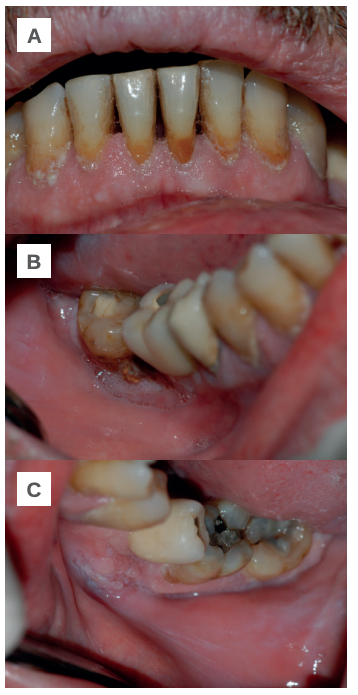

Tras la exploración intraoral se confirma que la mayor parte de las lesiones se localizan en el tejido gingival de la región antero-inferior, en mucosa yugal a nivel de los molares inferiores y en el fondo vestibular (Figuras 1-A, B y C). A la espera de un diagnóstico definitivo se le prescribe acetónido de triamcinolona 0,1%, con el que mejora en los tres días siguientes. Tras una nueva reagudización se intensifica el tratamiento corticoide suministrando dexametasona 4 mg inyectable (1 día/3 días) y 4 mg vía oral (1 día/5 días), con el que obtiene una notable mejoría durante las dos semanas siguientes.

A: región antero inferior. B: mucosa yugal derecha y fondo de vestíbulo. C: mucosa yugal izquierda y fondo de vestíbulo.

A nivel clínico la lesión primaria del PV es la ampolla, el resto de lesiones coalescentes (costras, erosiones y restos epiteliales) son el resultado de su evolución natural18. La ampolla suele presentar dimensiones variables, el contenido puede ser seroso, purulento o hemorrágico y puede asociarse a ampollas limítrofes con la sucesiva formación de placas erosivo-costrosas. En más del 50% de los casos el debut se localiza en la mucosa oral; según el área bucal interesada es posible encontrar erosiones irregulares, grandes y en ocasiones recubiertas por lesiones blanquecinas en la mucosa yugal; erosiones, costras y restos epidérmicos en labios; erosiones en el tejido gingival alrededor de los dientes; erosiones aisladas o coalescentes en paladar y erosiones especialmente dolorosas en la lengua19. En el PV cutáneo suelen localizarse en tronco, ingles, axilas, cuero cabelludo y cara20. Las lesiones observadas en este paciente afectaron a la mucosa yugal y a la encía del sector antero-inferior, constituyendo un límite importante para llevar a cabo una higiene oral adecuada y con la consecuente acumulación de placa en las caras vestibulares de sus dientes. No se registraron manifestaciones en el paladar, lengua o labios.